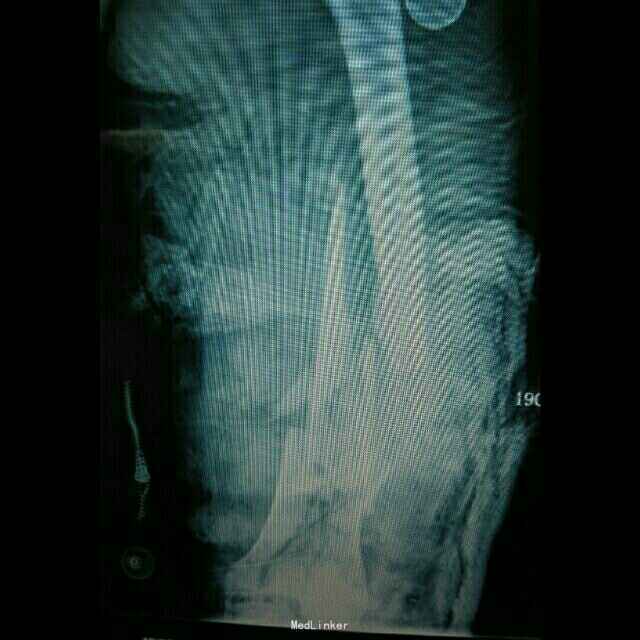

患者,女性,40岁,因车祸伤至左下肢大面积皮肤缺损伴多发粉碎骨折,右足大面积皮肤缺损 急诊入骨科,一期清创,骨牵引 二期拟双下肢截肢,请我科会诊,改行左侧截肢,左足组织移植修复右足

诊断:左下肢毁损伤 右足皮肤软组织缺损 予以行上述手术